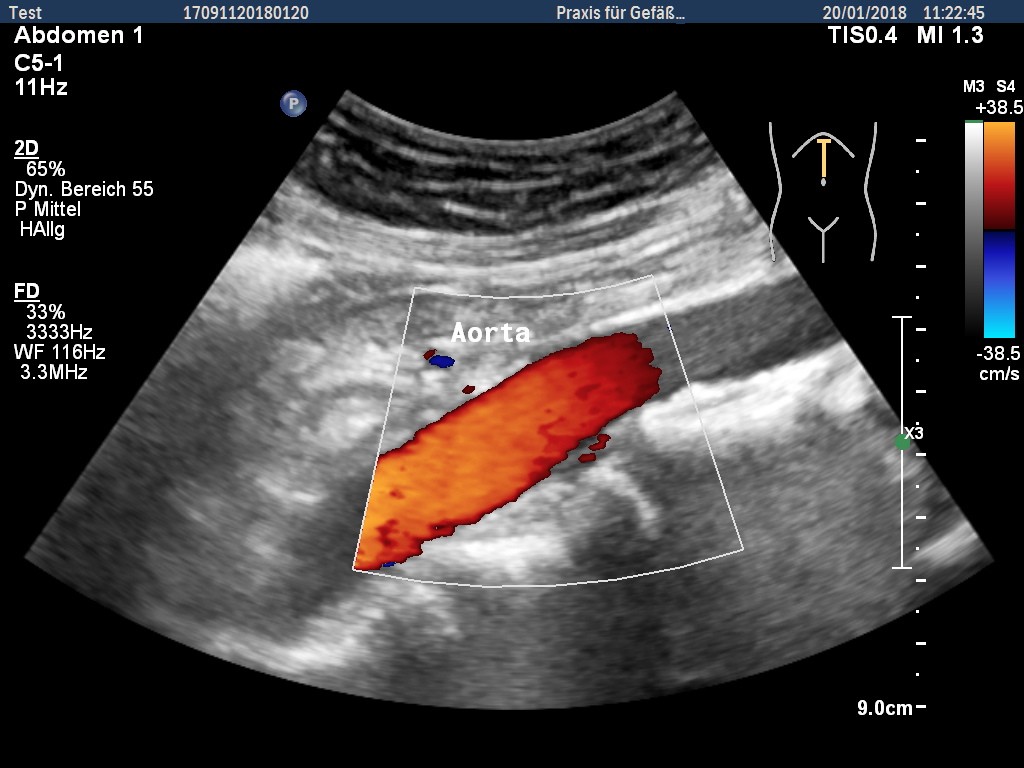

Ultraschall-Screening auf Erweiterung (Aneurysma) der Bauchschlagader (Aorta) als Versicherungsleistung der gKV.

Seit dem 01.01.2018 bieten die gesetzlichen Krankenversicherungen allen Männern ab 65 Jahren eine einmalige und kostenlose Ultraschall-Untersuchung der Bauchschlagader an.

Ziel ist es, eine mögliche Erweiterung (Aneurysma) der Bauchschlagader frühzeitig zu erkennen.